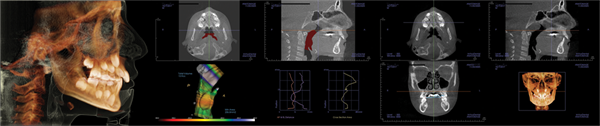

Patient three: Palatal expansion and Phase I (Figs. 8–11)

The third patient was referred for crowding. During the examination, the mother reported that the patient snored, experienced night terrors, and did not sleep well.

The facial examination showed an angular facial form, lack of a full smile, and crowding. A tongue tie was noted, along with a dark buccal corridor. The panoramic evaluation indicated nearly adequate room for the second molars and a Class II tendency. The lateral X-ray confirmed these findings.

The airway section of the CBCT demonstrated an MCA of 51 mm and enlarged tonsils and adenoids. The palatal width was 29 mm.

The family reported that the night terrors subsided and that sleep quality improved significantly over the following year.